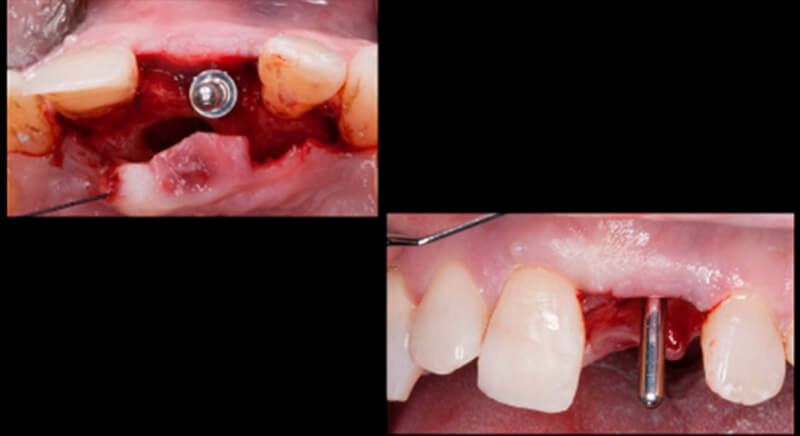

The guided surgery was performed by lifting a full thickness mucoperiosteal flap. A Biomimetic Ocean CC implant, diameter 3.5mm and length 10mm, was inserted using the surgical guide in the ideal three-dimensional position and the defects were regenerated with xenograft and reabsorbable membrane, the nasopalatine duct on the palatine side and the area of dehiscence on the vestibular.

During the same surgical intervention, a short 3mm Avinent healing abutment was positioned and fully covered by the flap. Primary closure was completed and we waited 6 months for the bone graft to mature.

After 6 months of healing, a minimum crestal incision was made to change the 3mm abutment underneath for a 5mm abutment that would be exposed to the oral medium.